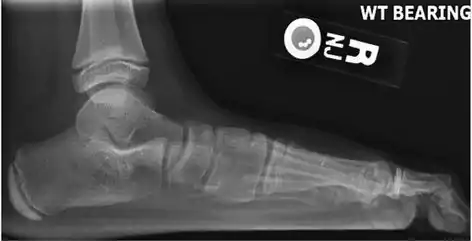

On plain radiography, flat feet can be diagnosed and graded by several measures, the most important in adults being the talonavicular coverage angle, the calcaneal pitch, and the talar-1st metatarsal angle (Meary's angle).[11] The talonavicular coverage angle is abnormally laterally rotated in flat feet.[11] It is normally up to 7 degrees laterally rotated, so a greater rotation indicates flat feet.[11] Radiographies generally need to be taken on weightbearing feet in order to detect misalignment.[12]

Weight-bearing lateral X-ray showing the measurement of calcaneal pitch, which is an angle of the calcaneus and the inferior aspect of the foot, with different sources giving different reference points.[13] A calcaneal pitch of less than 17° or 18° indicates flat feet.[11]

Same lateral X-ray showing the measurement of Meary's angle, which is the angle between the long axis of the talus and first metatarsal bone.[11] An angle greater than 4° convex downward is considered a flat foot, 15° - 30° moderate flat foot, and greater than 30° severe flat foot.[11]